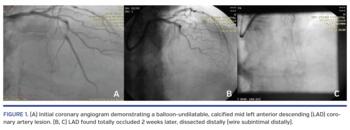

A 65-year-old patient with a significant stenosis of the mid left anterior descending (LAD) coronary artery was referred to our cath lab for percutaneous coronary intervention (PCI) with rotational atherectomy, after a failed initial PCI attempt in a peripheral hospital, in which this heavily calcified mid LAD lesion proved to be balloon-undilatable (Figure 1A).

In our cath lab, upon initial angiographic assessment, we discovered that the vessel was totally occluded. The occluded lesion was approached with antegrade wire escalation using sequentially an Asahi Fielder XT wire, an Abbott Hi-Torque Pilot 200 wire, and finally an Asahi Confianza/Conquest Pro 12 wire. During the attempt, the vessel was dissected, and we therefore tried the subintimal tracking and re-entry technique, attempting wire-based re-entry to get into the true lumen. Unfortunately, this resulted in dissection enlargement and hematoma propagation in the distal vessel (Figures 1B and 1C; Video 1), even though we repeatedly aspirated the intramural hematoma.